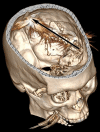

BACKGROUND Penetrating traumatic brain injury (TBI) caused by gunshots is a rare type of TBI that leads to poor outcomes and high mortality rates. Conducting a formal neuropsychological evaluation concerning a patient's neurologic status during the chronic recovery phase can be challenging. Furthermore, the clinical assessment of survivors of penetrating TBI has not been adequately documented in the available literature. Severe TBI in patients can provide valuable information about the functional significance of the damaged brain regions. This information can help inform our understanding of the brain's intricate neural network. CASE REPORT We present a case of a 29-year-old right-handed man who sustained a left-hemisphere TBI after a gunshot, causing extensive diffuse damage to the left cerebral and cerebellar hemispheres, mainly sparing the right hemisphere. The patient survived. The patient experienced spastic right-sided hemiplegia, facial hemiparesis, left hemiparesis, and right hemianopsia. Additionally, he had severe global aphasia, which caused difficulty comprehending verbal commands and recognizing printed letters or words within his visual field. However, his spontaneous facial expressions indicating emotions were preserved. The patient received a thorough neuropsychological assessment to evaluate his functional progress following a severe TBI and is deemed to have had a favorable outcome. CONCLUSIONS Research on cognitive function recovery following loss of the right cerebral hemisphere typically focuses on pediatric populations undergoing elective surgery to treat severe neurological disorders. In this rare instance of a favorable outcome, we assessed the capacity of the fully developed right hemisphere to sustain cognitive and emotional abilities, such as language.